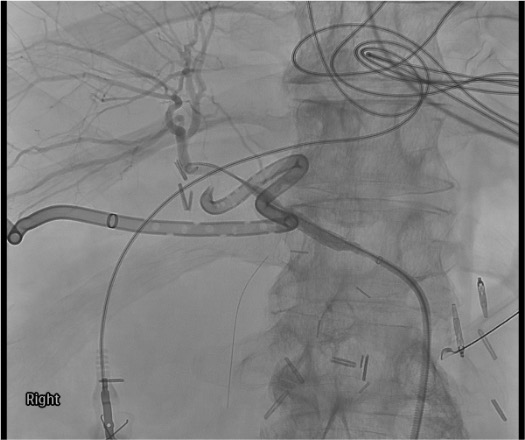

- Covered stent principle: Stent is placed in CHA spanning the GDA stump origin, maintaining hepatic perfusion while excluding the bleeding stump. Hepatic flow is preserved — liver does not lose its blood supply.

Covered stent deployment

Completion angiogram

- Stent migration — particularly in infected field; monitor on CT at 24–48h

- CT at 24–48h: confirm stent position, hepatic perfusion, resolution of pseudoaneurysm, exclude hepatic infarct